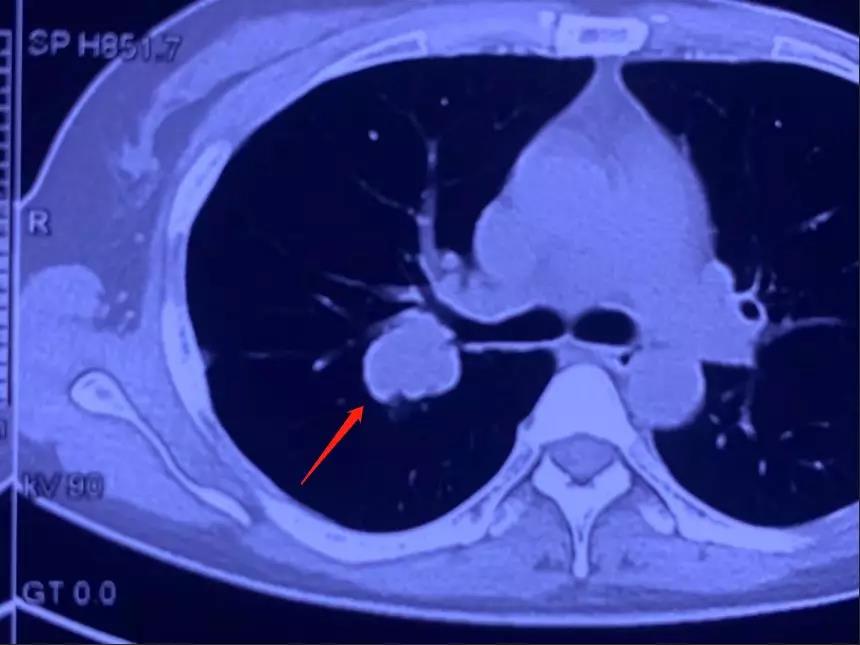

前几日,复大肿瘤医院来了一位乳腺癌患者刘阿姨。刘阿姨之前做了手术,后来出现复发情况。通过检查发现,右肺靠肺门的地方出现了转移,由于所处于的位置比较特殊,实施传统手术需要切除一个肺叶,这样会对刘阿姨的身体伤害很大。复大的专家团队对刘阿姨的病例进行了分析讨论,认为在这种情况下,消融是一个很好的选择。

刘阿姨在半年前因为肺部的转移已经做过一次消融,那个病灶控制的比较好。而这次这个病灶是新生的,所以复大的专家团队决定还是采取消融的方法来处理。手术由牛立志教授主刀,牛立志教授在CT引导下将冷冻针插进了病灶,因肿瘤靠近肺门,所以牛教授将针插进肿瘤边上,避免伤及气管,手术非常顺利,病灶被消灭,刘阿姨身体状况良好。